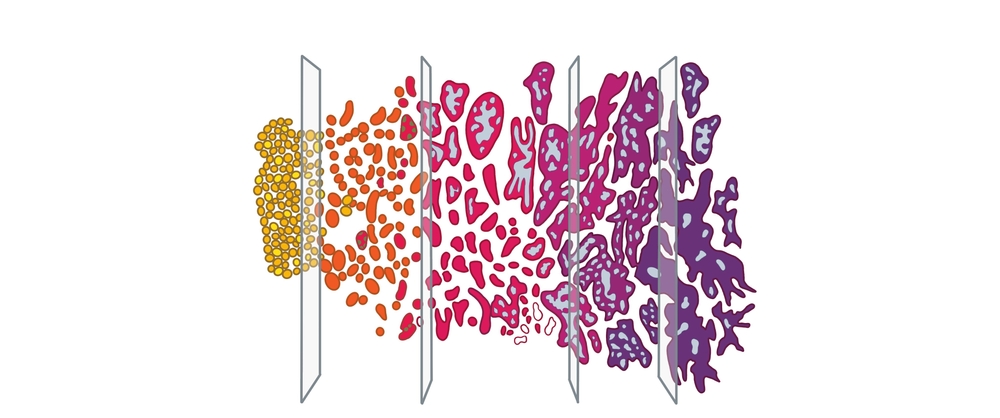

Cancer Grading

Grading refers to the way cancer looks under a microscope. When abnormal-looking cancer cells are found, the pathologist ranks them according to the degree of visible change. While early-stage or low-grade cancer cells may look only slightly different from healthy cells, high-grade cancer cells look dramatically different. Each of the tissue samples collected during a biopsy is assigned a number according to the Gleason Grade from 3 to 5 if cancer is present. The number 3 indicates the “least aggressive” grade of prostate cancer, while the number 5 represents the “most aggressive” grade of the disease.